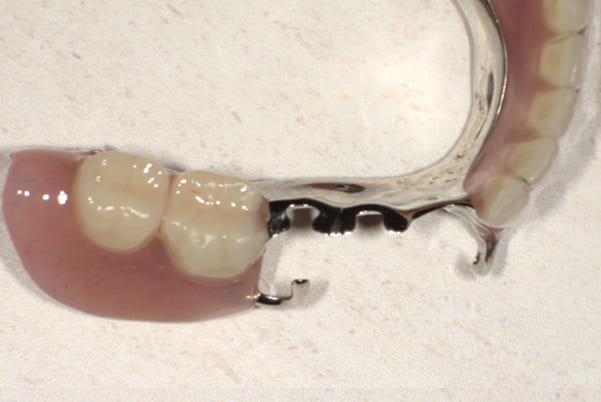

ご自身の歯に負担の少ないバネ、また見た目も改善

ご自身の歯に負担の少ないバネ

バネをかける歯は繋げることで強度を増し、歯への負担を軽減し、歯の寿命を長くする設計へ。

バネがかかる歯の被せ物は、歯への負担を減らし、入れ歯が動きにくいようになる形態をあらかじめ付与することで、より入れ歯の機能が高まります。

治療を行う際、被せ物や入れ歯は、別々に考えるのではなく、一口腔単位としてお口全体のことを考え最良の治療計画を立てることが歯の寿命、機能効果を向上させるため、専門医としてこのことは常に心掛けて治療を行っています。